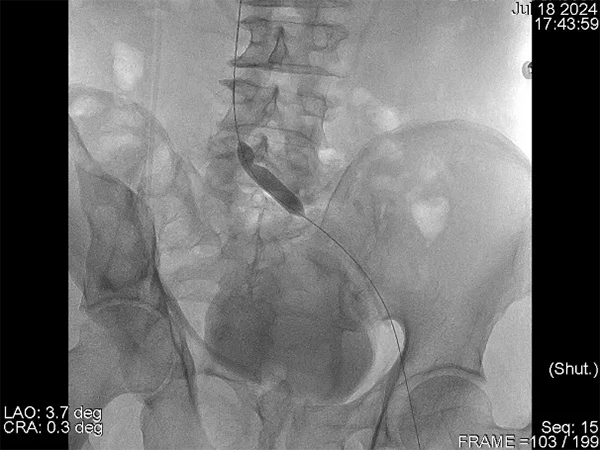

在與患者及家屬進行了詳細的交流后,患者決定住院治療。在經(jīng)過了詳細的病情分析后,介入科肖晉昌團隊為其制定了“髂靜脈造影+球囊擴張+支架置入”的治療計劃。術(shù)中造影發(fā)現(xiàn)患者左髂總靜脈近心端重度狹窄,周圍側(cè)支開放,狹窄兩端壓差明顯,均提示患者存在重度的髂靜脈壓迫(圖3)。予以球囊擴張狹窄處(圖4),然后行支架置入(圖5)。支架置入后造影患者左髂靜脈血液回流明顯改善,周圍側(cè)支減少。術(shù)后由張科醫(yī)師負責對其隨訪,經(jīng)過1個月的隨訪,患者目前下肢潰瘍基本愈合(圖6)。

圖4 球囊擴張